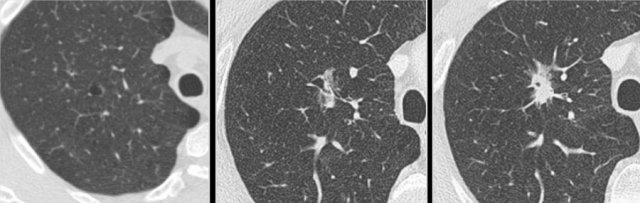

Ví dụ minh họa sự chuyển đổi từ hình thái dạng nang (bảng trái và giữa) sang hình thái ung thư phổi bán đặc (bảng phải).

Các nốt dạng nang có thể biểu hiện sự gia tăng thành phần đặc, xuất hiện thêm thành phần kính mờ và thành phần nang, đồng thời thể tích tổn thương tổng thể cũng tăng lên.

Các nghiên cứu hồi cứu đã chứng minh rằng ung thư phổi dạng nang có thể phát triển từ các tổn thương tiền thân bán đặc kích thước nhỏ, cũng như có thể chuyển đổi từ các tổn thương tiền thân dạng nang thành ung thư đặc hoặc bán đặc tại thời điểm chẩn đoán.

Do đó, hình thái ung thư phổi mang tính linh hoạt và các thành phần dạng nang có thể chỉ là tạm thời.

Ví dụ này minh họa sự chuyển đổi từ hình thái bán đặc (bảng trái), sang hình thái dạng nang tạm thời (bảng giữa), rồi đến hình thái ung thư phổi đặc (bảng phải).

Ví dụ minh họa sự chuyển đổi từ hình thái kính mờ thuần túy (bảng trái) sang hình thái ung thư phổi dạng nang (bảng phải).